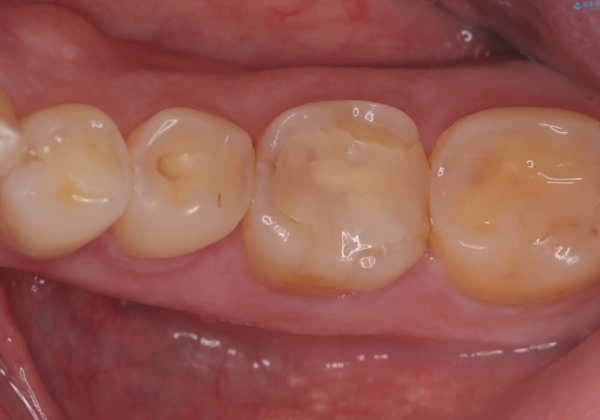

咬合力によるヒビの部分に生じる歪みを軽減するため、クラウンを被せました。

咬合力によるヒビの部分に生じる歪みを軽減するため、ヒビを追えるところまで切削しCR裏層・支台歯形成を行い、一度仮歯に置き換え症状の緩和を確認し、CAD/CAM冠を装着しました。